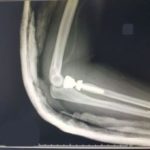

Kolejny nowatorski zabieg w brzeskim szpitalu

Tym razem zespół ortopedów, którym kieruje lek med. Krzysztof

Szklanny wykonał operację wielokrotnie złamanego łokcia. Pacjentce,

która przeszła zabieg, wszczepiono endoprotezę głowy kości promieniowej.

–...